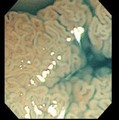

食管憩室

十二指肠球部溃疡

结肠癌

腺瘤

食管静脉曲张

食管炎

溃疡性结肠炎

锯齿状腺瘤

管状腺管腺瘤

小肠绒毛及淋巴滤胞

小肠绒毛

绒毛状腺瘤

肠息肉

直肠癌

增生性息肉